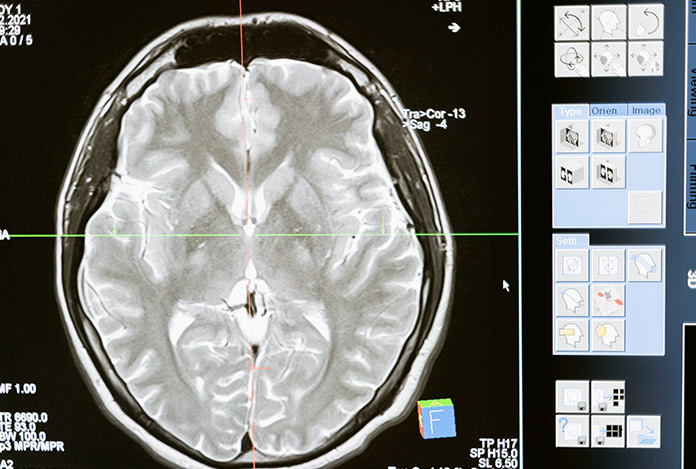

Covid-19 beyinde kalıcı etki bırakıyor mu?

Covid-19’u ağır geçiren hastalarda bütün vücut gibi beynin de bu süreçten etkilendiğini belirten Türk Nöroloji Derneği Başkanı Prof. Dr. Mehmet Akif Topçuoğlu, “Beyin indirekt şekilde etkileniyor ama beyin iltihabı ve diğer açılardan bir etkilenme söz konusu değil” dedi.

NTV’nin haberine göre, Türk Nöroloji Derneği Başkanı Prof. Dr. Mehmet Akif Topçuoğlu, Covid-19’un beyin üzerinde uzun dönemli etkileri olup olmadığına yönelik değerlendirmelerde bulundu. Covid-19’u ağır geçiren hastalarda bütün vücut gibi beynin de bu süreçten etkilendiğini ama farklı şiddetli hastalıklarda da aynı durumun görülebildiğini belirten Topçuoğlu, “Beynimizdeki 86 milyar nöron içerisinde Covid-19’un içeriye girişini sağlayacak reseptörler bulunmuyor. Fakat virüs, bu bölgedeki damarlar ve destek hücrelerinde bulunabiliyor. Dolayısıyla beyin indirekt şekilde etkileniyor ama beyin iltihabı ve diğer açılardan bir etkilenme söz konusu değil” diye konuştu.

BU YÖNDE BELİRTİ YOK

Topçuoğlu, Covid-19’un beyin üzerinde uzun dönemli, kalıcı hasarlara yol açıp açmayacağının tıp çevrelerince hala tartışıldığını, net bir kanıya henüz varılamadığını anlatarak, “Şu anda ibre, Covid-19 açısından beynin, akciğer gibi diğer organlara göre biraz daha şanslı olduğu, beynin bu süreçten daha düşük düzeyde etkilendiği yönünde. 2 yıldır pandeminin uğultusu altında yaşıyoruz, bugüne kadar çok vaka gördük. Eğer beyin üzerinde sık görülen, hepimizi korkutacak ciddi bir etkilenim olsaydı şimdiye kadar belirtileri de fazlasıyla görülürdü. Çok şükür bu yönde belirtiler yok” sözlerini kaydetti.